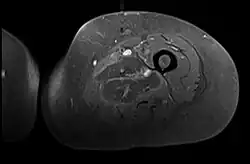

Axial fat suppressed T2 weighted MRI image showing hyperintense signal and enlargement of the left thigh adductor muscle group in diabetic myonecrosis.